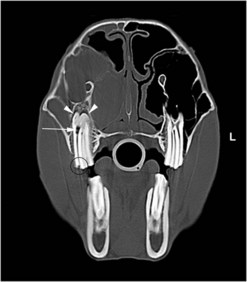

Odontogenic tumors

Tumors of dental-tissue origin are all rare, but may be more common in horses than in other species20 and are discussed in detail in Chapter 11. Five types of odontogenic tumors have been recorded in horses, and their radiological characteristics have been reviewed in detail.21 Ameloblastomas and ameloblastic odontomas can have a similar radiographic appearance.21 They are expansive, soft-tissue opacity masses containing lytic areas and sometimes areas of irregular granular calcification21 and often displace adjacent teeth (Fig. 13.42). Complex and compound odontomas are irregular, tumor-like masses of dental tissues in well differentiated forms (Fig. 13.43). Complex odontomas contain all the elements of a normal tooth but within a disorganized structure, hence radiologically they appear as multiple, small, lobulated radio-opaque masses within a well-defined cyst-like structure.20,21 In contrast, compound odontomas contain an orderly pattern of dental tissues which form recognizable tooth-like structures. Cementomas are very radio-opaque mineralized structures, often rounded in appearance and associated with chronically infected tooth apices (Fig. 13.41F) or their alveoli following extraction of the infected tooth.

image image image

Fig. 13.43 Radiograph (A) and CT images (B and C) of a compound odontoma in a 2-year-old TB colt.

(Images courtesy of J. Easley.)